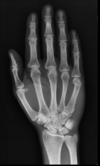

10

Colles’ fracture

**Colles - ‘dinner fork type deformity’** Features of the injury 1. Transverse fracture of the radius 2. 1 inch proximal to the radio-carpal joint 3. Dorsal displacement and angulation of the distal radius

Colles fracture ## Footnote Typically FOOSH forwards Extra-articular radial # with dorsal (posterior / back of hand) angulation and displacement